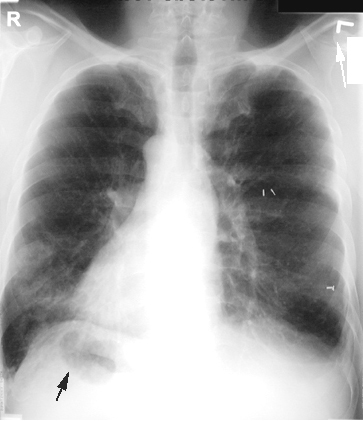

Immotile Cilia Syndrome: Situs Ineversus Totalis

Dextrocardia. Stomach bubble on right. Surgical clips from previous lobectomy for bronchiectasis. Bronchiectasis cannot be recognized from this CXR.